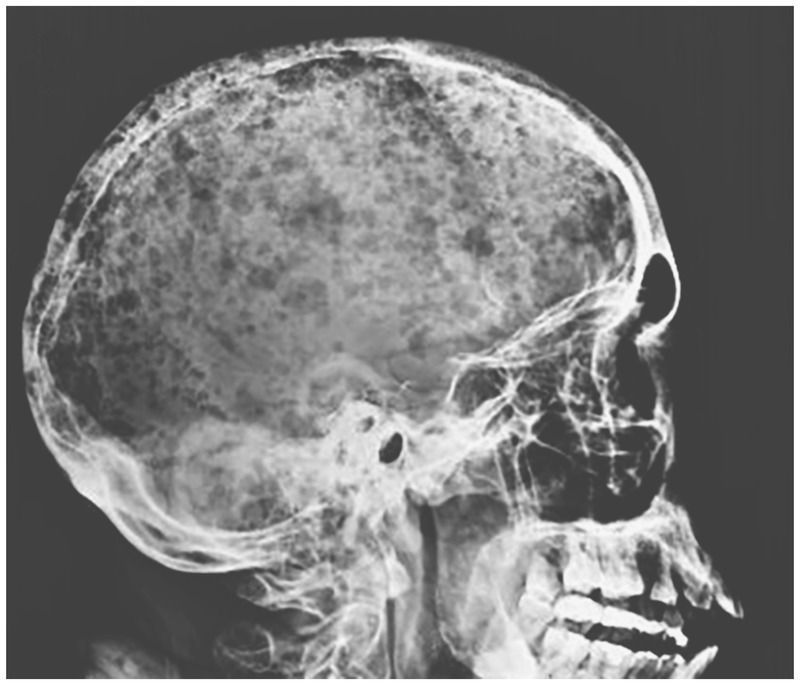

A 46-year-old man presented to the emergency department with a 1-month history of fatigue, shortness of breath, and low back pain and report of a weight loss of 30 kg over the previous 10 months. On physical examination, his conjunctiva and palms were pale. Laboratory evaluation revealed a hemoglobin level of 4.9 g per deciliter (reference range, 12 to 16), a creatinine level of 5.4 mg per deciliter (480 μmol per liter; reference range, 0.4 to 1.0 mg per deciliter [35 to 88 μmol per liter]), and a calcium level of 12 mg per deciliter (3 mmol per liter; reference range, 8.9 to 10.3 mg per deciliter [2.2 to 2.6 mmol per liter]). A skeletal survey showed diffuse osteopenia, a pubic bone fracture, and numerous radiolucent lesions on the skull, which had an appearance known as “raindrop skull” — a pattern of lytic or punched-out lesions that resemble raindrops hitting a surface and splashing. These findings are characteristic of multiple myeloma. The diagnosis was confirmed by bone marrow biopsy and aspirate samples that showed 50% clonal plasma cells in the marrow; serum protein electrophoresis revealed a monoclonal IgA paraprotein. Initial management included red-cell transfusion for treatment of anemia and hydration to correct hypercalcemia. The patient did not respond well to induction therapy and died 3 months after diagnosis.